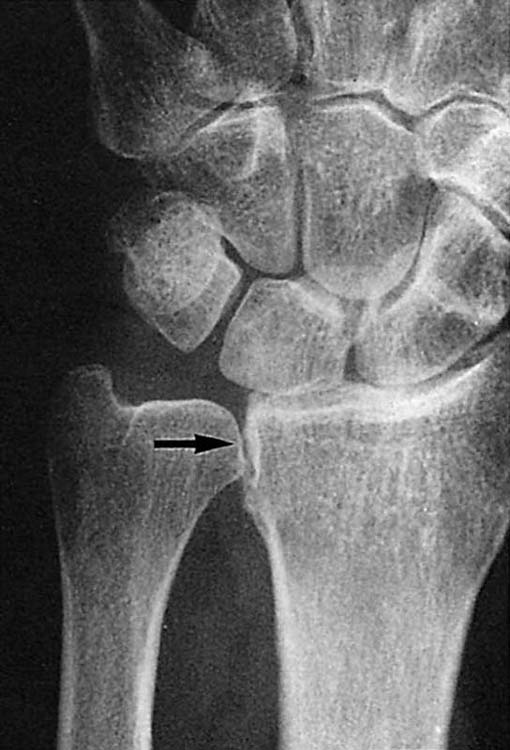

Figure 13-4 This posteroanterior view of the wrist shows a fracture of the proximal third of the scaphoid (arrow) with an associated cyst.

images